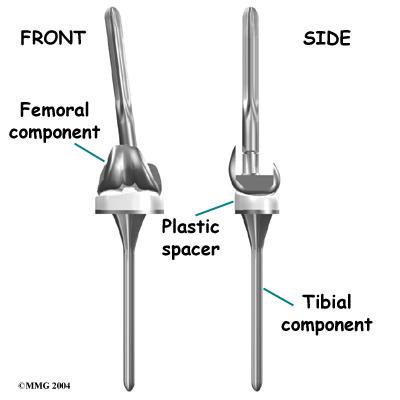

Each prosthesis is made up of three main parts.

The tibial component (bottom portion) replaces the top surface of the lower bone, the tibia. The stem of the tibial component used in revision surgery is usually much longer than the type used for primary knee replacements. This is because the bone of the tibia is usually not the same as when the initial replacement was done. The bone may be weaker, or there may be areas inside the tibia where bone is missing. A longer stem can reach further down the tibial canal and distribute your body weight better. It also gives the body a greater surface area for healing, which can improve fixation of the implant to the bone inside the tibia.

The femoral component (top portion) replaces the bottom surface of the upper bone (the femur) and the groove where the patella fits. Like the tibial component used in revision, the femoral component often has a long stem.

The patellar component (kneecap portion) replaces the surface of the patella where it glides in the groove on the femur.

The tibial component is usually made of two parts: a metal tray that is attached directly to the bone, and a plastic spacer that provides the slick surface. The femoral component is made of metal. In some types of knee implants, the patellar component is made of a combination of metal and plastic.